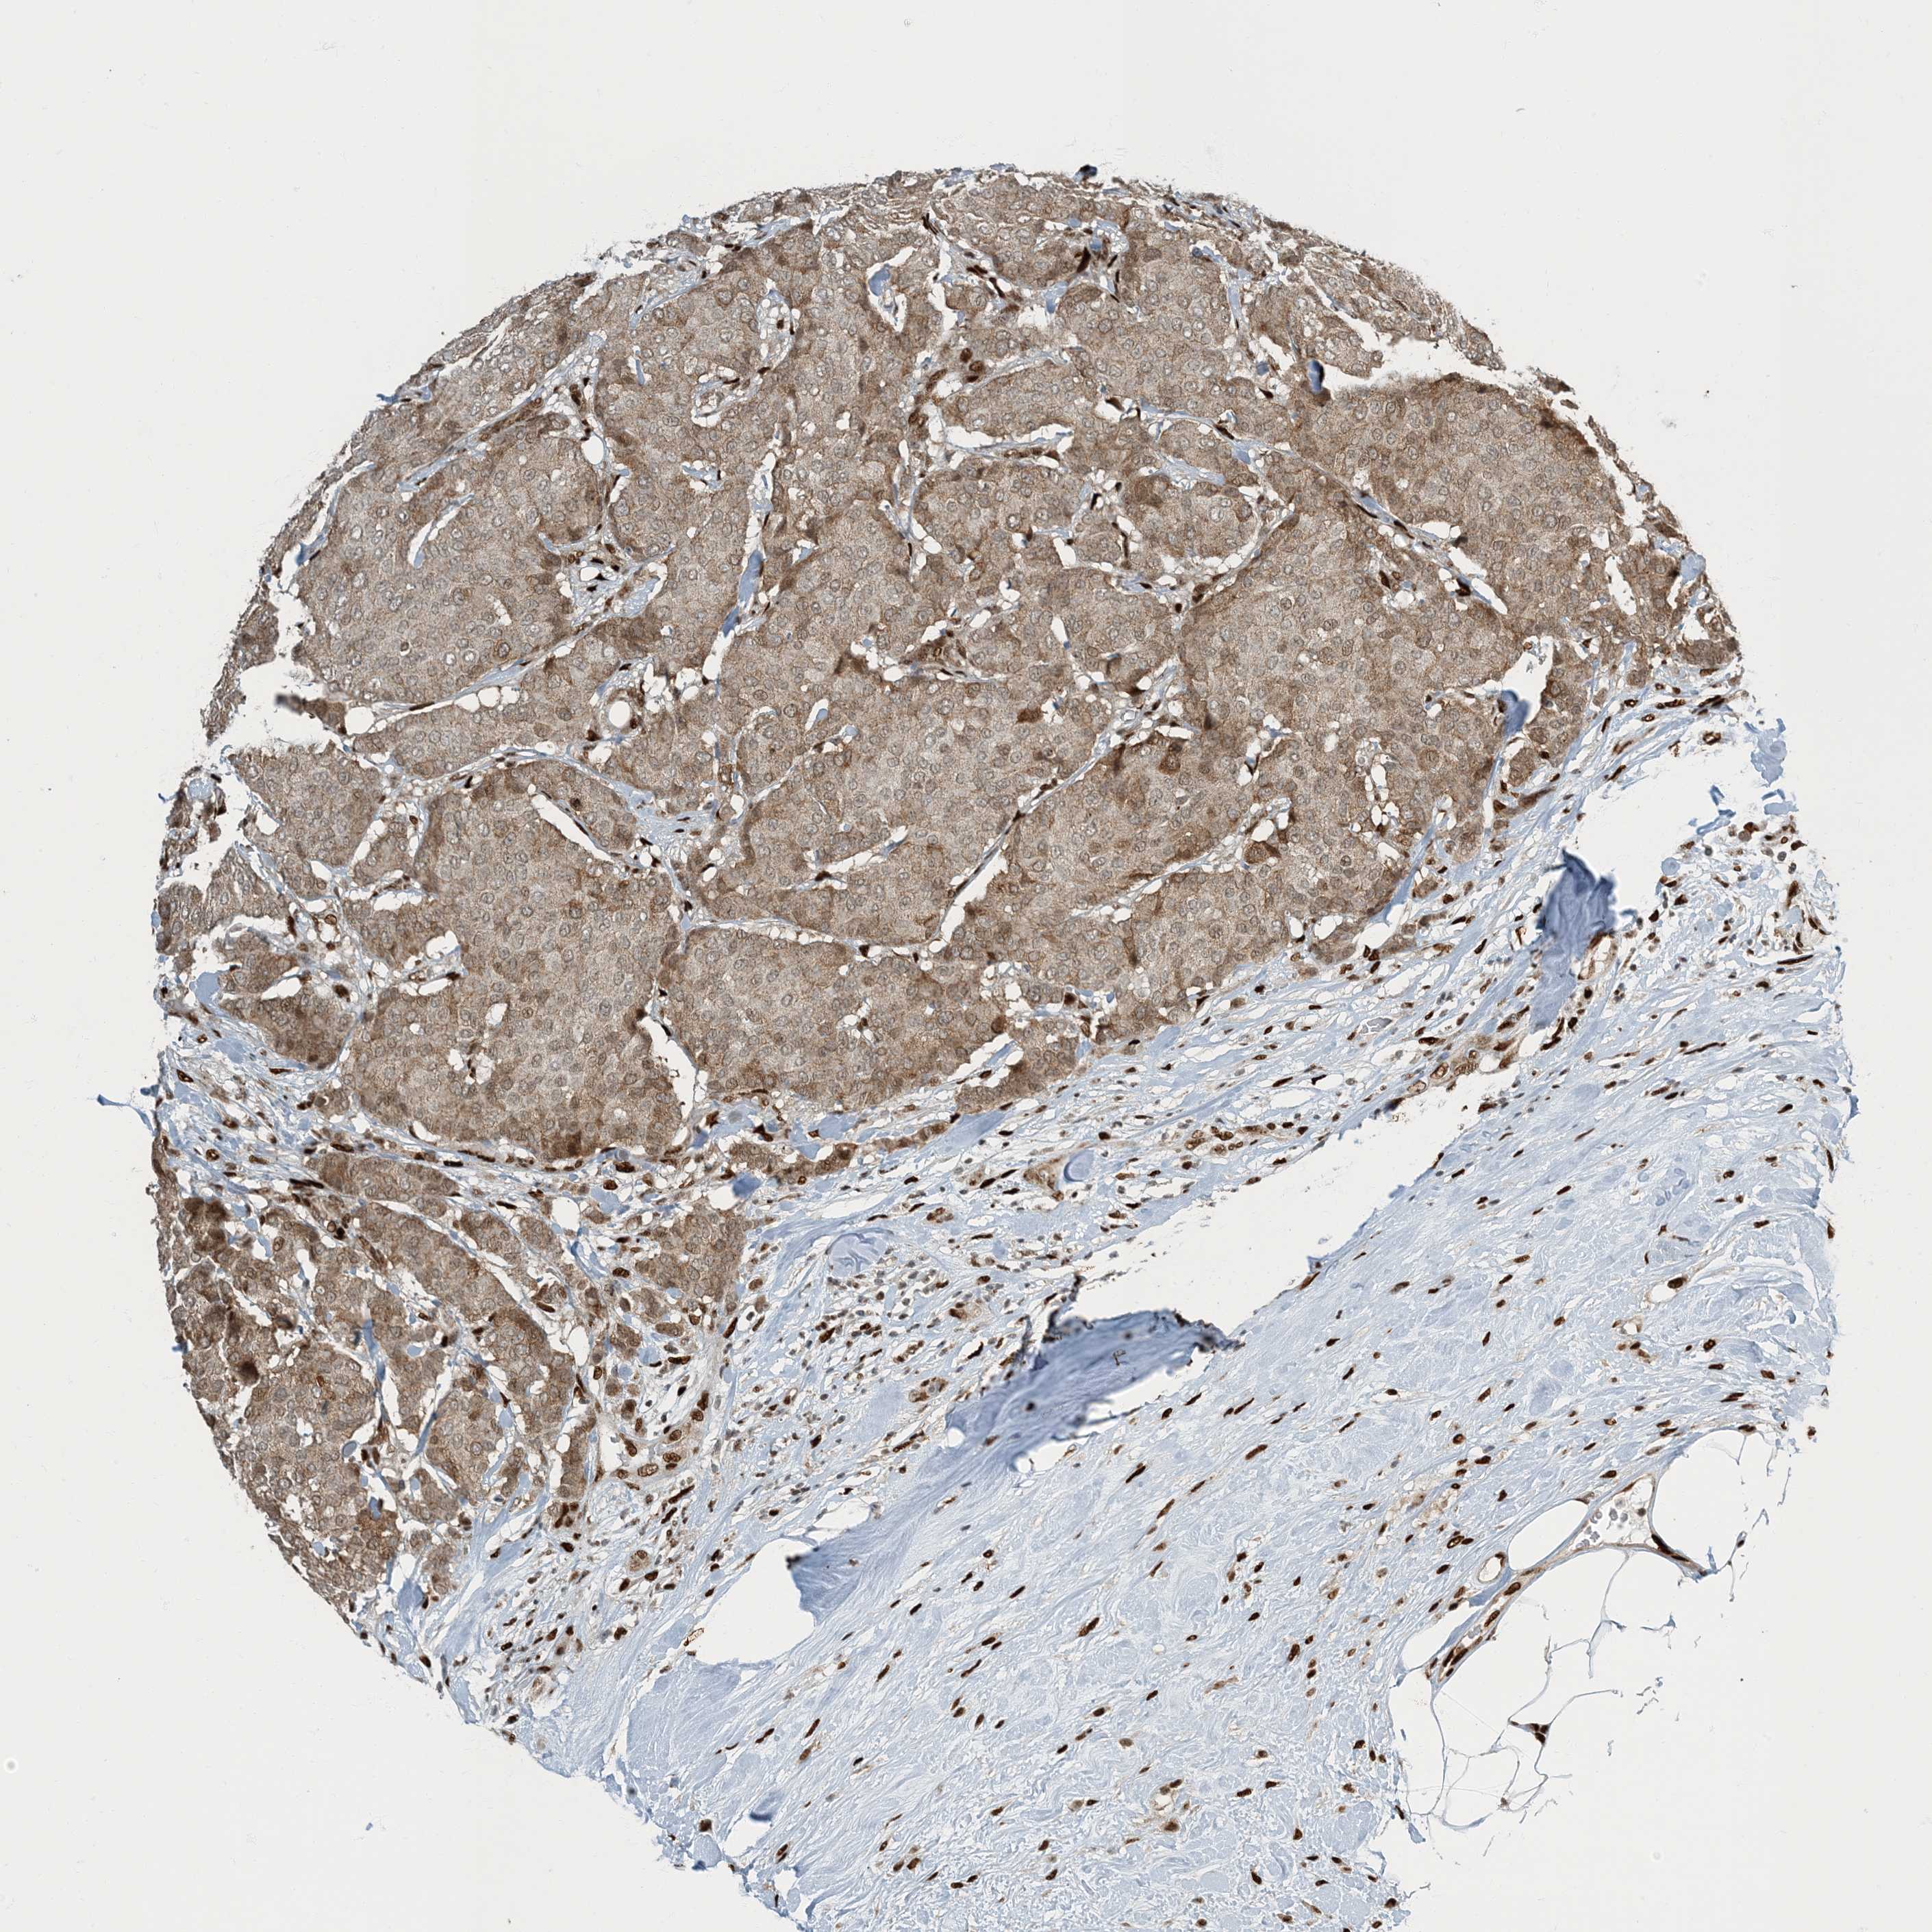

CANCER BREAST CANCER Show tissue menu

BRCA TCGA BRCA VALIDATION PROTEIN EXPRESSION